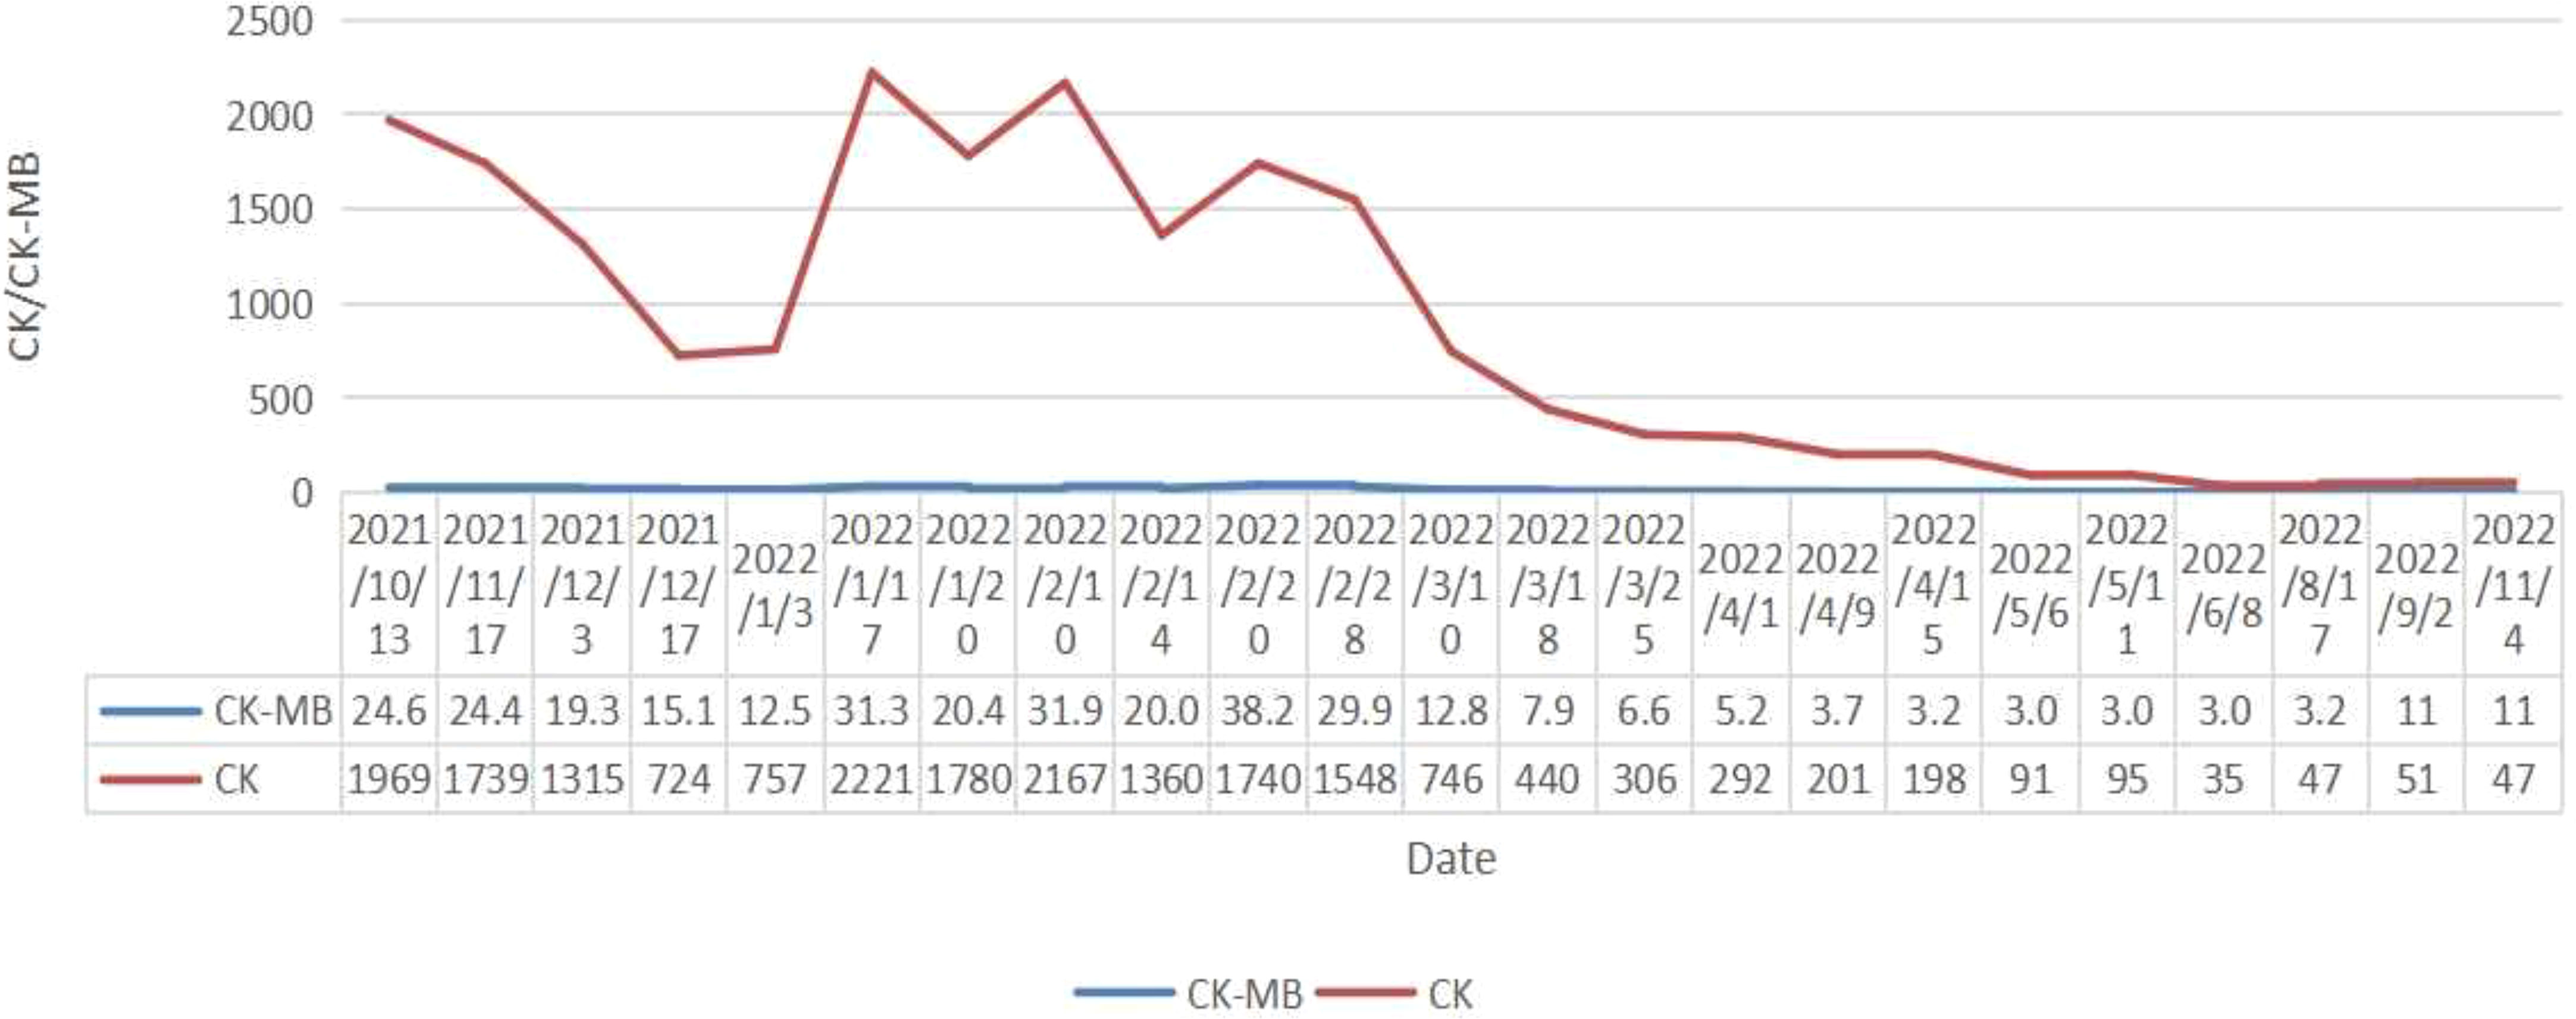

Coloscopy was performed, and pathological analysis of the tumor revealed adenocarcinoma (Figures 1C, D). Immunohistochemistry showed positivity for MLH1, MSH2, and MSH6 and negativity for PMS2. Next-generation sequencing confirmed that the tumor was MSH-H. However, the patient refused immunotherapy. Thus, a first cycle of chemotherapy consisting of mFOLFOX6 plus bevacizumab was administered on 1 October 2021. After three cycles, an abdominal CT scan showed an impressive reduction in tumor size in the right colon, while the retroperitoneal lesion remained stable. A chest CT revealed interstitial pneumonia (Figure 2), but the patient did not experience dyspnea. A multidisciplinary team (MDT) discussion, including surgical staff, was organized to formulate further treatment plans. Specialists recommended pembrolizumab, nivolumab, or nivolumab in combination with ipilimumab—all approved therapies for patients with metastatic MSI-H/dMMR colon cancer regardless of their eligibility for intensive therapy. Since the patient could not afford the expenses of the recommended courses of treatment, envafolimab was suggested instead. With patient and treatment teams reaching an agreement, the patient was started on envafolimab (150 mg, administered subcutaneously, once weekly) on 21 September 2021. Interstitial pneumonia did not worsen over the course of treatment, as evidenced by chest CTs. One month later, the patient experienced pain in her extremities with elevated creatine kinase (CK) and creatine kinase isoenzyme MB (CK-MB) levels. No significant laboratory findings involving cardiac troponins or N-terminal pro-brain natriuretic peptide were observed. We consulted cardiologists in our hospital. who excluded the possibility of ICI-related myocarditis but suspected myositis. However, she refused a proposal of muscle biopsy. According to the Management of Immune Checkpoint Inhibitor-Related Toxicity section of the Guidelines of the Chinese Society of Clinical Oncology, the symptom is classified in Grade 1, for which dose reduction or discontinuation are not considered. Therefore, nonsteroidal anti-inflammatory drugs (NSAIDs) and low-dose methylprednisolone (12 mg daily) were administered, and immunotherapy was continued. Decreased CK and CK-MB were observed three days after management (Figure 3). On 1 March 2022, a CT scan showed a decrease in volume, prompting a second MDT to suggest the patient continue treatment. A greater reduction in lesion size was observed during a follow-up CT scan in May 2022. Moreover, envafolimab with methylprednisolone (4 mg, daily) was well tolerated. Thirty-six cycles later, the lesion in the right colon disappeared on an abdominal CT scan performed on 18 August 2022 (Figure 4). Post-treatment colonoscopy revealed no neoplasm, and immunohistochemistry revealed chronic mucositis (Figures 1E, F). PET/CT also showed that the patient achieved CR efficacy (Figure 1B). Given the safety of envafolimab, the patient was started on 400 mg of envafolimab every 3 weeks without additional adverse events. CK and CK-MB levels remained low.

In this case, our patient developed interstitial pneumonia after two cycles of mFOLFOX6 and bevacizumab. While the component causing pulmonary toxicity was unknown, a few reports have found bevacizumab and leucovorin to cause lung damage (15, 16). Conversely, oxaliplatin may have been the toxic agent, as the pulmonary disease did not recur with oxaliplatin-free chemotherapy but did with 5FU and leucovorin (17, 18). Though pulmonary toxicity from FOLFOX is uncommon, it could be lethal despite the discontinuation of the agents and the initiation of immunotherapy. Considering the reasonable safety of envafolimab, with no immune-related pneumonitis in its phase 2 study, it was used to treat the patient (3). Fortunately, the interstitial pneumonia did not worsen. Our patient was administered a subcutaneous injection of 300 mg Q3W when CK and CK-MB trended toward stability. Moreover, the fixed-dose schedule prevented additional adverse events and proved efficacious and convenient. Notably, the patient also developed immunotherapy-induced myositis, a rare condition typically only seen in a case series. While immune-related myositis was not observed in the envafolimab clinical trial, it has been reported as a complication of other ICIs. Among 9,088 patients receiving ICIs at the MD Anderson Cancer Center, 0.4% were diagnosed with ICI-myositis, 0.94% with combination ICI therapy, and 0.31% with ICI monotherapy. The delay between ICI initiation and myositis onset was approximately one month. Moreover, the onset of myalgia during ICI-myositis was quicker than that in primary autoimmune polymyositis (19). Reported symptoms characteristic of ICI-myositis include myalgia, limb-girdle weakness, and oculomotor weakness with diplopia (20). The outcomes of patients with only elevated CK, including those who needed short hospitalizations for CK normalization, were more favorable than those of patients with overlapping syndromes (21). Further studies are needed to clarify the mechanism of ICI-myositis, the biomarkers to predict, and the time to rechallenge ICIs.